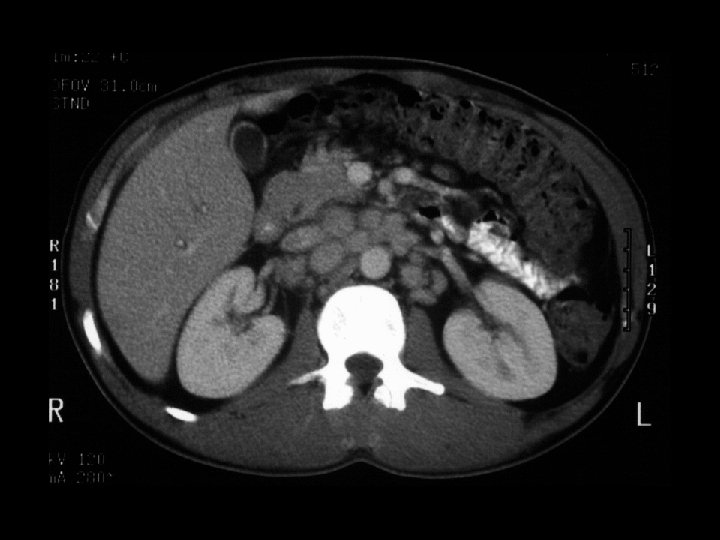

Neuroblastoma • Findings: – Bone scan shows increased uptake in the mid abdomen of a child – MR scan shows a corresponding soft tissue mass with scattered T 1 low sign foci = Ca 2+ • ddx: – NONE! – This is an Aunt Minnie!